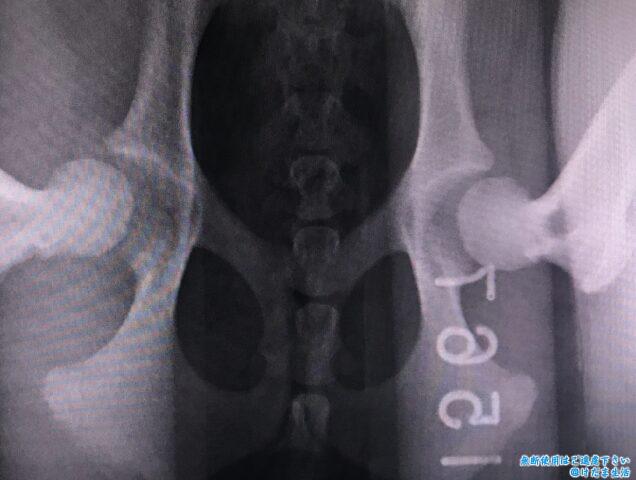

普通の仰向けの姿勢と、

足を器具で広げた状態。

寛骨臼から大腿骨頭が外れているのが分かります。